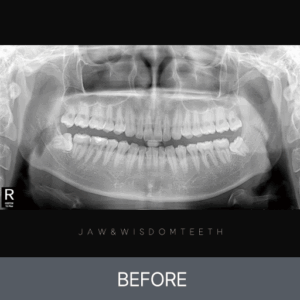

턱관절 CASE